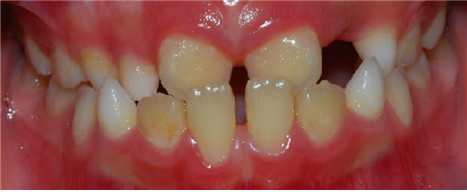

| 치료전: 위아래의 앞니들은 영구치들로 반대교합으로 되어 있고, 좌우 하얀 색의 치아들은 아직 젓니인 상태로 남아 있다. |